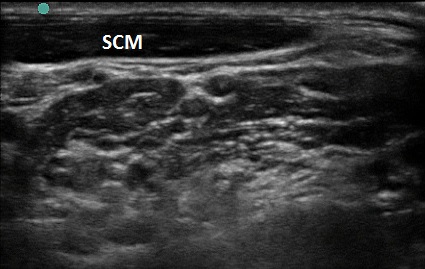

Figure 1. Transverse view over the sternocleidomastoid

- Use a high-frequency 8-12 MHz linear probe and begin scanning transversely over the anterior neck at the level of the cricoid. (Figure 1)

- Probe indicator oriented to operator’s left.

- Depth should be set between 4-8 cm, depending on the size of the patient’s neck.

- Trachea should be clearly seen as a midline hyperechoic arc.

- Slide the probe laterally to the lateral border of the sternocleidomastoid (SCM) (Figure 1), which is a thin muscle superficial to the carotid and jugular.

- Move the probe inferiorly to identify the anterior scalene muscle deep to the lateral border of the SCM. (Figure 2)

- Triangular muscle that is thicker caudally

- Lateral to the internal jugular vein

- If not apparent, slide the probe in a cranio-caudal direction along the lateral border of the SCM to find it